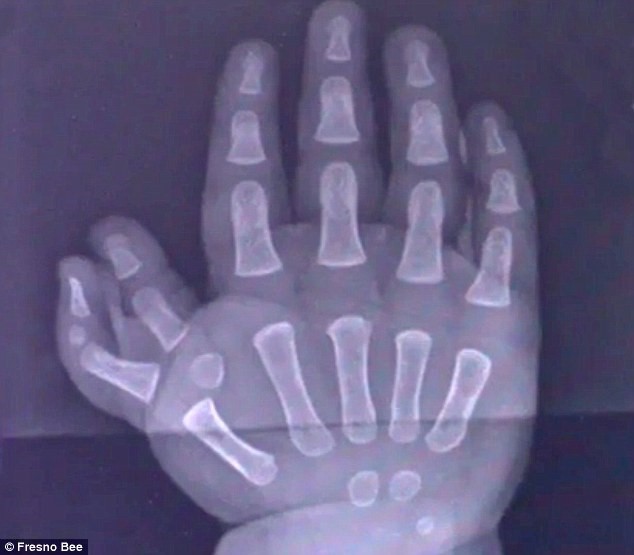

Bản chụp X-quang một bàn tay của Kyrie. Ảnh: Presno Bee.

Cậu bé Kyrie Carter (Fresno, California, Mỹ) sinh ra với 2 ngón tay cái trên tay phải và 3 ngón tay cái trên tay trái. Ngày 16//2017, Kyrie trải qua ca phẫu thuật tách bỏ ngón tay thừa trên bàn tay phải. 2 ngón thừa bên bàn tay trái đã được loại bỏ trong một ca phẫu thuật tháng 8/2016.

Polydactyly là một trong những khiếm khuyết bẩm sinh phổ biến nhất hiện nay, với tỷ lệ 1/1.000 trẻ sơ sinh mắc. Polydactyly có thể được phát hiện bằng siêu âm ngay khi còn trong bụng mẹ và bằng mắt thường ngay sau khi đứa trẻ chào đời. Bác sĩ chụp X-quang để đánh giá cấu trúc ngón của bé để xác định một phương pháp điều trị cụ thể.